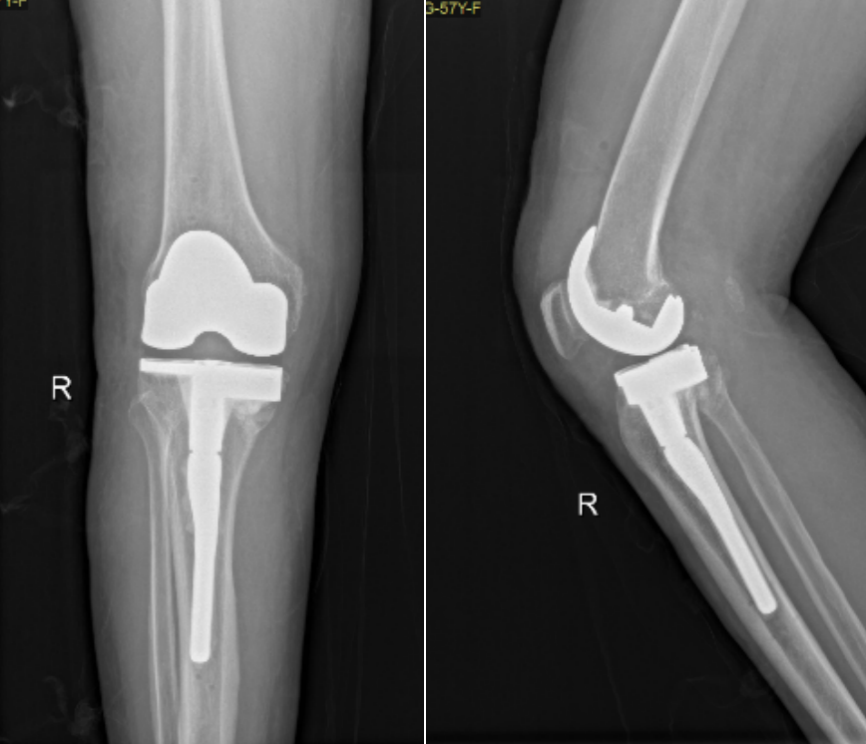

在这些数据的基础上,团队制定了“人工膝关节置换 + 骨缺损修复”同步进行的创新手术方案,力求最大程度解决问题。

在机器人的辅助下,医生团队的系列操作降低了创伤性关节炎的发生风险以及二次手术的可能性,辅以科学系统的康复训练,张阿姨的关节稳定性和活动能力在一天天稳步恢复,如今,她已能够自如地行动,安享舒适惬意的晚年生活。

而对于陈旧性胫骨平台骨折合并严重骨关节炎的患者,机器人辅助手术有着精准、可控等优势,张还添介绍,机器人技术能同步完成关节置换和骨缺损修复,减少软组织干扰与骨质损伤,进一步降低术后风险,为患者争取更稳定长久的关节功能。